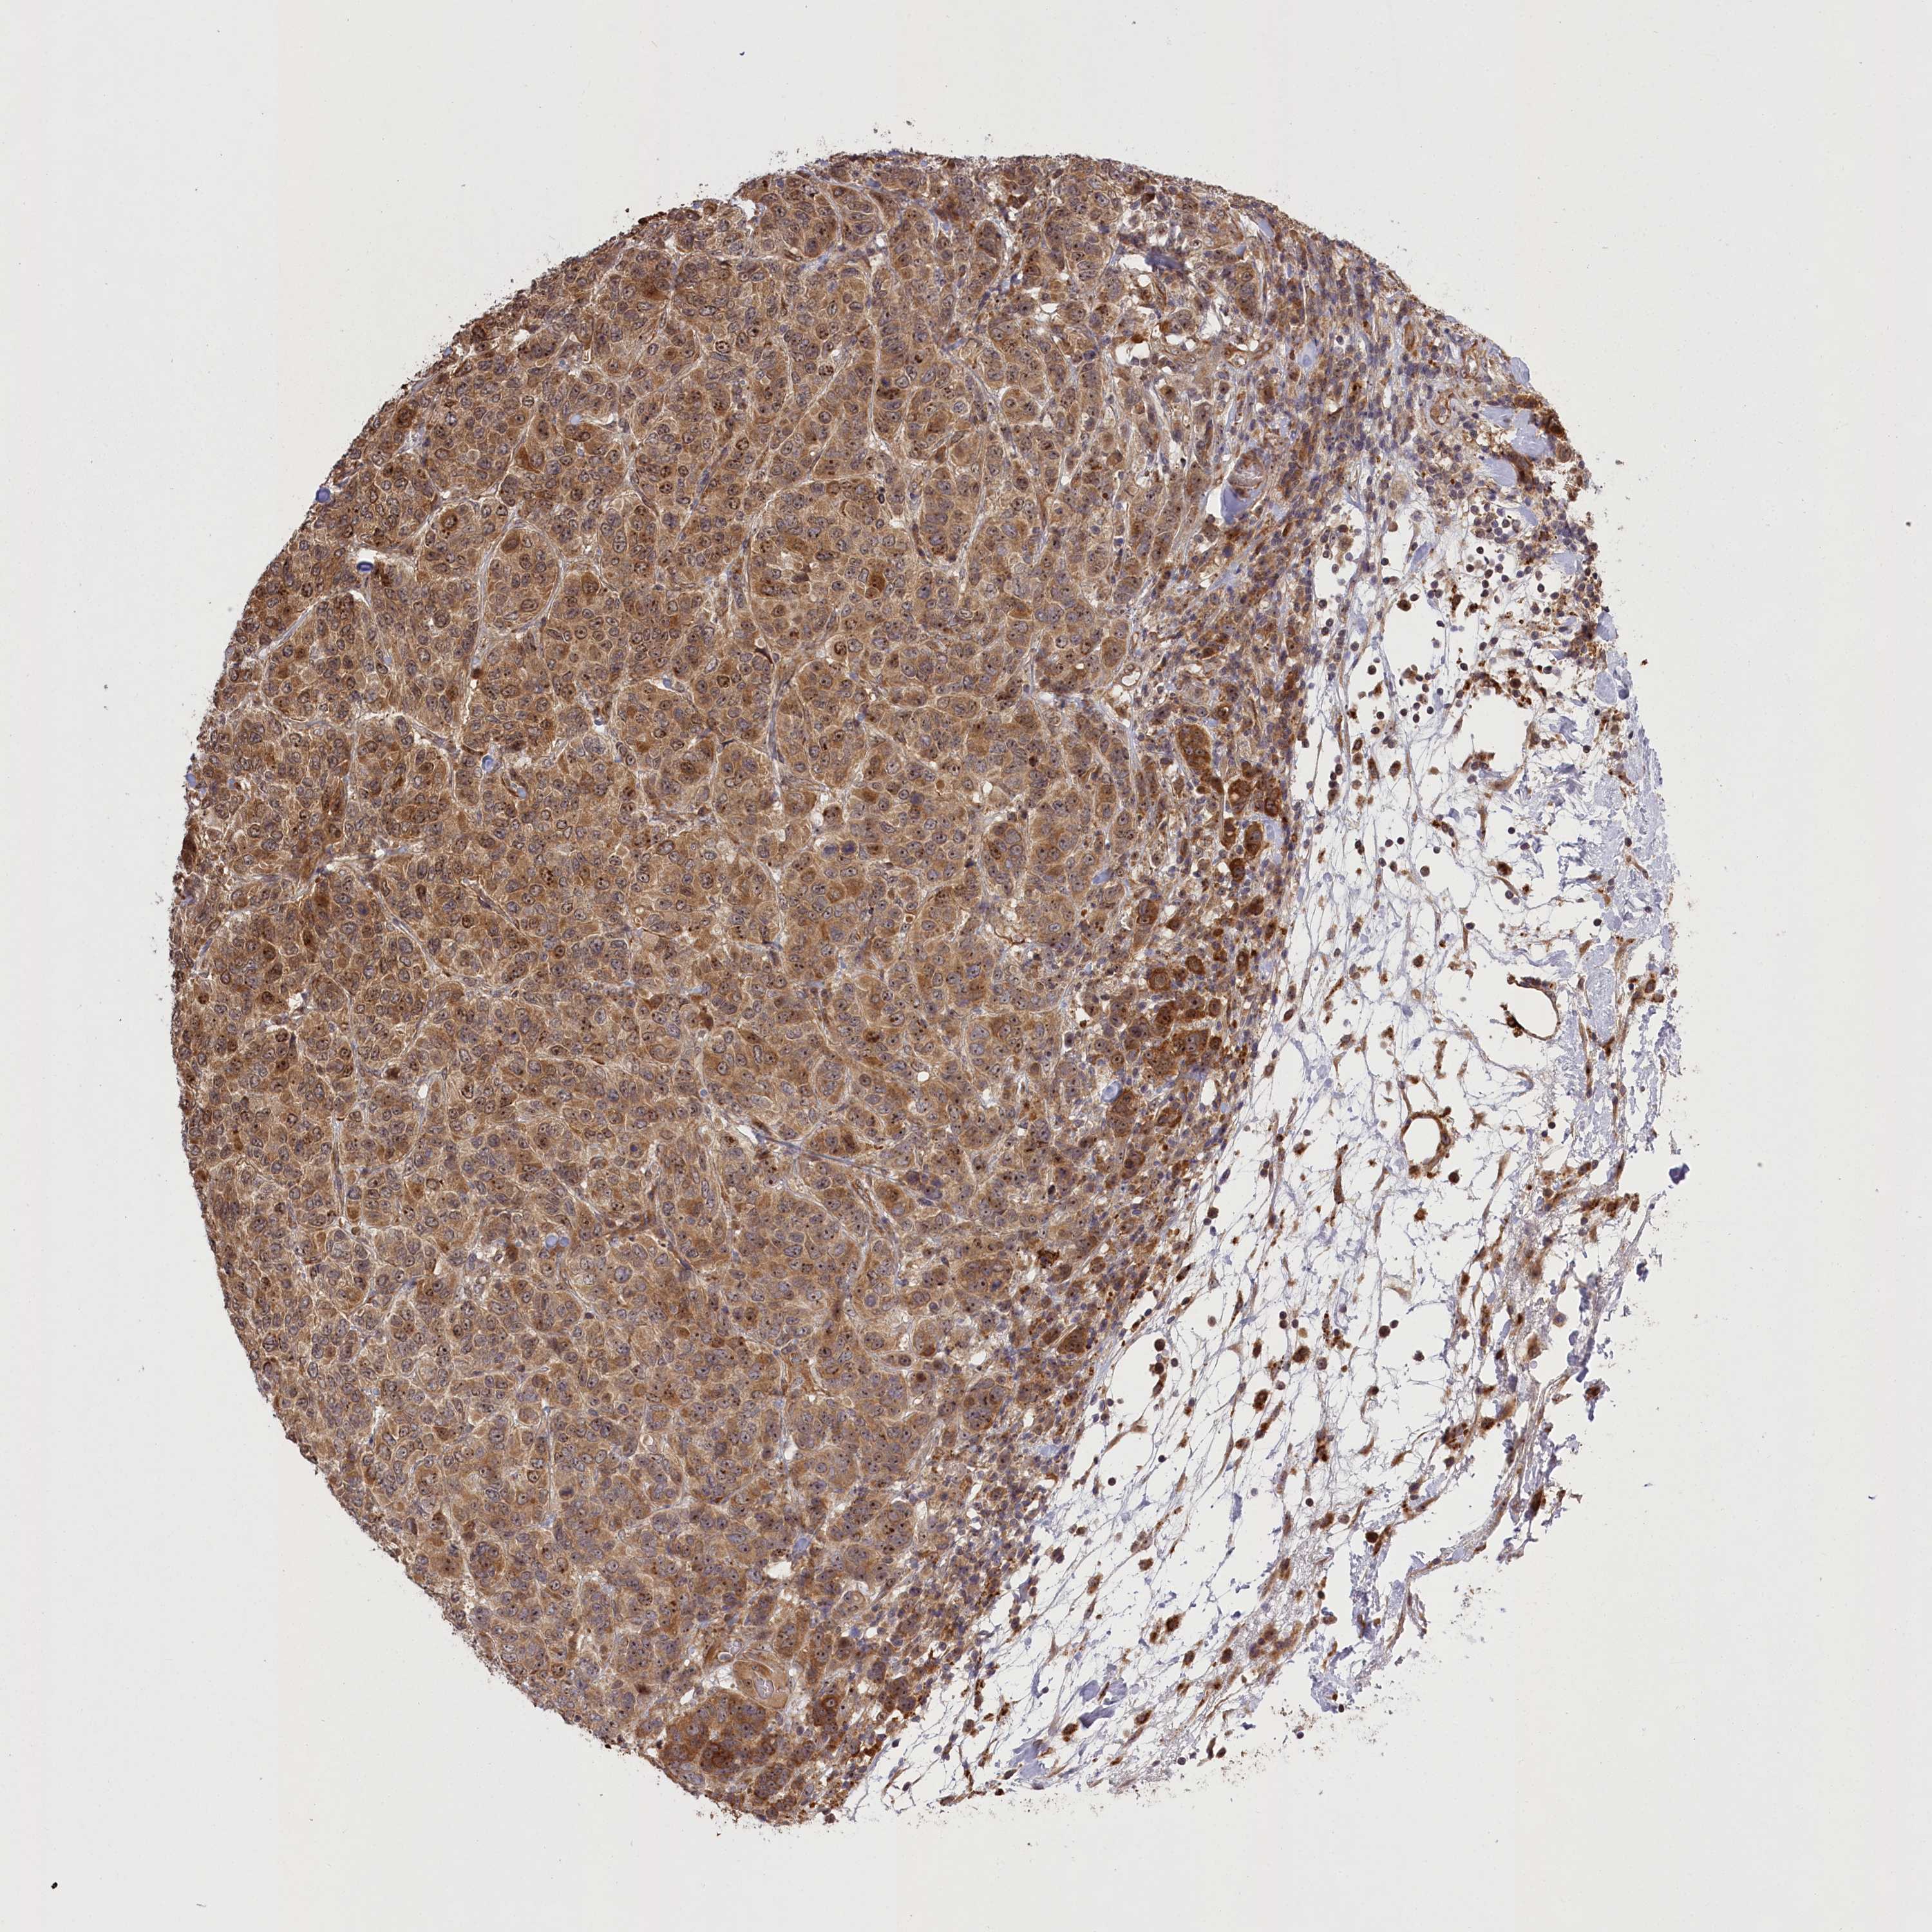

CANCER BREAST CANCER Show tissue menu

BRCA TCGA BRCA VALIDATION PROTEIN EXPRESSION